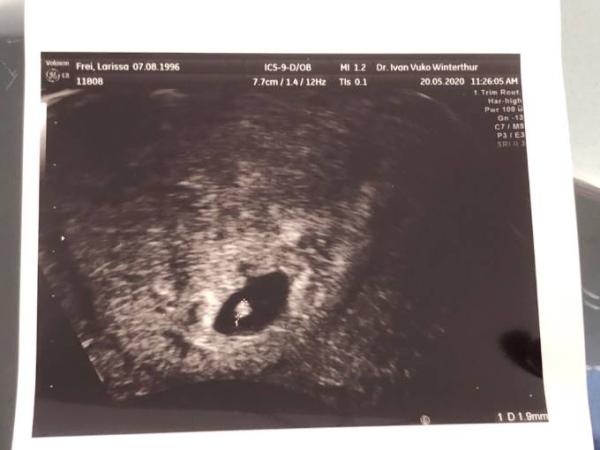

er het zwei Embryos gesehen bei dem einen (1.9mm) schlägt das Herz sehr stark

(Fotos beim Post ist vom grösseren, im Kommentar vom kleineren (zu langsamer Herzschlag)

da es das Bild nicht angenommen hat, poste ich beide in den Kommentaren, also zuerst das grössere: